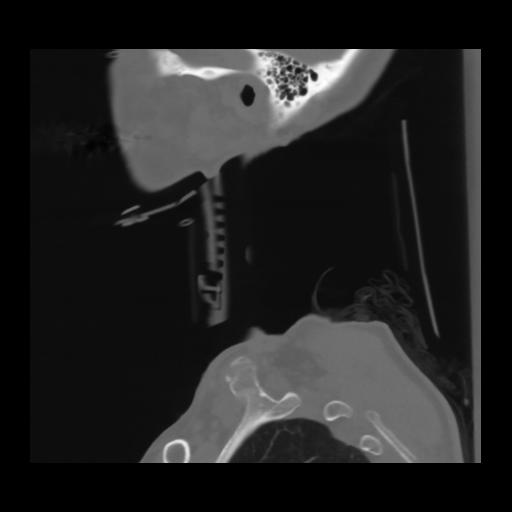

14 P.BLANDAS,,Sagittal,2.000,P.BLANDAS,Sagittal,